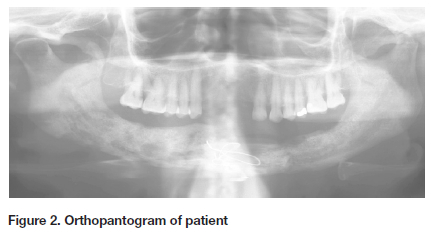

Special investigations included an Orthopantomogram (OPG) radiograph which showed multiple areas of ill-defined, moth-eaten mixed radiolucent/radiopaque lesions extending from the left parasymphaseal area of the mandible to the symphysis (Figure 2). A pathological fracture was noted in the midline of the mandible that had been reduced and fixed with wire. Microscopy, culture, and sensitivity (MC&S) results that accompanied the patient from a private laboratory, showed multiple drug resistance. The list included resistance to penicillin and beta-lactamase.